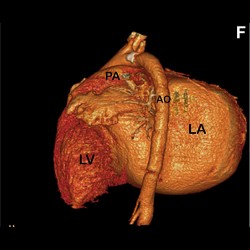

Giant Left Atrium Due to Rheumatic Mitral Regurgitation

Giant Left Atrium Due to Rheumatic Mitral Regurgitation

Giant Left Atrium Due to Rheumatic Mitral Regurgitation

Giant Left Atrium Due to Rheumatic Mitral Regurgitation